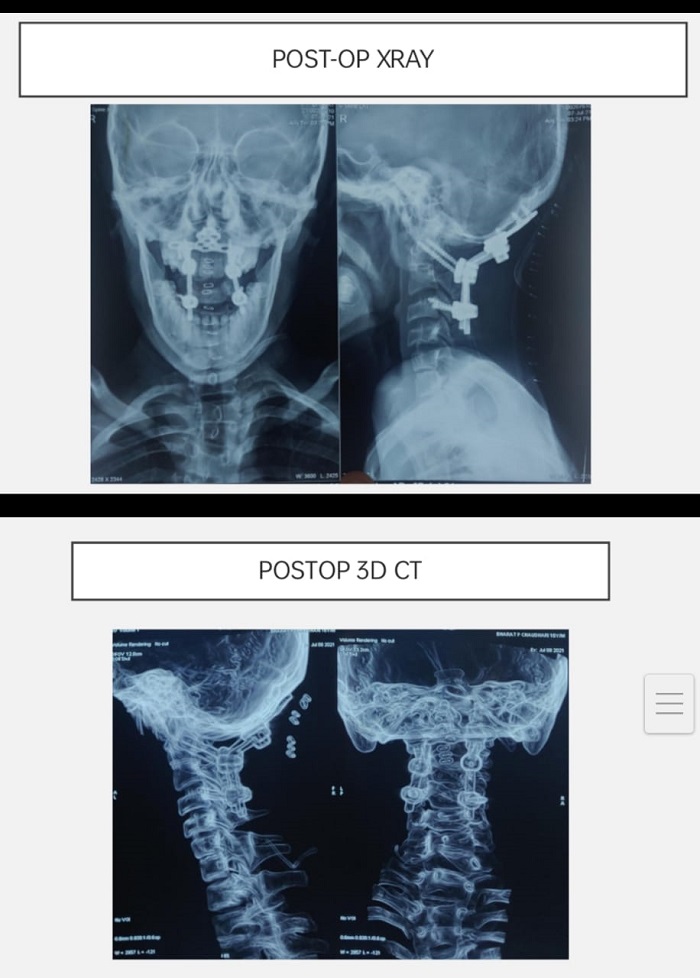

ભરતના પરિવારજનો વિનાવિલંબે ભરતને લઇને અમદાવાદ સિવિલ હોસ્પિટલ આવી પહોચ્યા. અહીં તેઓએ સ્પાઇન સર્જરી વિભાગના તબીબોનો સંપર્ક કર્યો. જ્યાં તબીબોએ રોગની ગંભીરતા પારખીને એક્સ-રે, સી.ટી.સ્કેન અને એમ.આર.આઇ.જેવા રીપોર્ટસ કરાવ્યા. આ રીપોર્ટસના આધારે સિનિયર તબીબ સહિત તમામે ભરતના રોગની ગંભીરતા અને જટીલતાનું અનુમાન લગાવ્યું.

આ રીપોર્ટસના આધારે ભરતના ગરદનનો પહેલો અને બીજા મણકો ખસી ગયેલ હોવાનું જણાઇ આવ્યું. જેને તબીબી ભાષામાં “એટલાન્ટો એક્સીઅલ ડીસલોકેશન” કહેવામાં આવે છે. આ પ્રકારની ઇજાની સર્જરી ખરેખર ખૂબ જ જટીલ હોય છે. કારણ કે આવા પ્રકારની સર્જરી દરમિયાન કરોડરજ્જૂના ભાગમાં પણ ઇજા થવાની સંભાવના રહેલી હોય છે.

સમગ્ર સર્જરી 2 કલાક ચાલી હતી.આ સર્જરી દરમિયાન જાણવા મળ્યું કે,ગરદાનના મણકો મગજના ભાગ સુધી પહોંચ્યો હતો. જેના કારણે સર્જરી અતિગંભીર બની રહી હતી. આ સ્તરે સર્જરી દરમિયાન જીવનનું જોખમ પણ વધી ગયુ હતુ. જેથી ન્યુરોમોનીટરીંગ સાથે સમગ્ર સર્જરી સફળતાપૂર્વક પાર પાડવામાં આવી. હાલ ભરતભાઇ સંપૂર્ણપણે સ્વસ્થ છે અને તેમના ગરદનના મણકા પૂર્વવત થયા છે. તેઓ પહેલાની જેમ જ સરળતાથી હલન-ચલન કરવા સક્ષમ થયા છે.